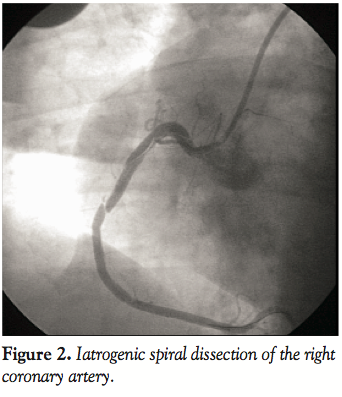

Case Report. A 42-year-old woman with hypertension presented with 8 months of typical angina. She was referred for an outpatient coronary angiography. The right dominant coronary artery showed no significant disease (Figure 1). Shortly after engagement of the left coronary artery, she developed chest pain, hypotension and new ST-segment elevation in both the precordial and inferior leads. Left coronary angiogram revealed TIMI 3 flow without any evidence of complications, including dissection or thrombosis. Left ventriculogram showed normal left ventricular ejection fraction (LVEF) without any wall motion abnormalities. Symptoms and ST-segment elevation persisted. Repeat RCA angiogram showed an extensive spiral dissection extending from the ostium to the distal RCA, with flow-limiting occlusion in the 3 marginal branches (Figure 2). The dissection was successively treated with direct stenting with 3 bare-metal stents (Figure 3).